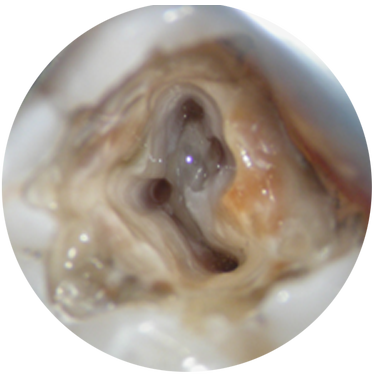

Endodontics - The Latest Irrigation, Instrumentation & Obturation Techniques

What’s the best way to irrigate the canal? What are the advantages of bioceramic-based products in obturation techniques? This program will review some basic principles of cleaning, shaping, and ob...